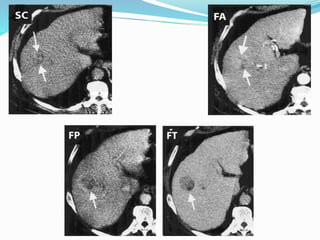

Tomografía Computarizada

Sensibilidad 50 % (37-94 %)

Especificidad 79 %

Helicoidal, multicorte, estudios dinámicos, angio-TC

4 fases: arterial precoz, parenquimatosa, venosa-portal

precoz y tardía

Tomografía Computarizada Sensibilidad 50% (37-94 %) Especificidad 79 % Helicoidal, multicorte, estudios dinámicos, angio-TC 4 fases: arterial precoz, parenquimatosa, venosa-portal precoz y tardía